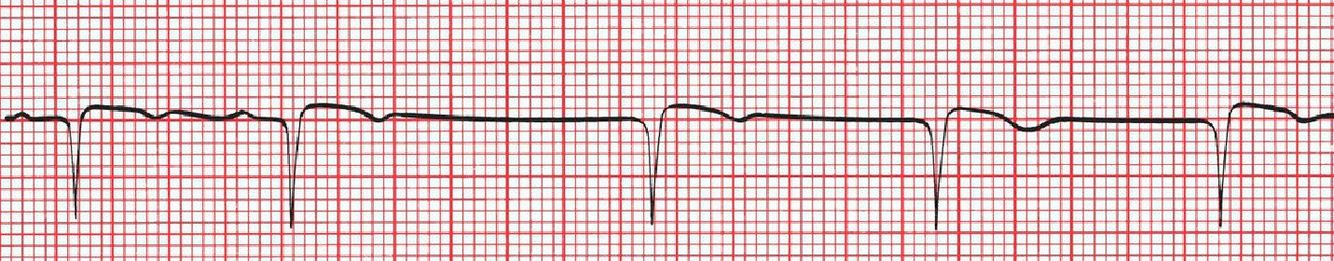

When would you see EKG like this?

A surgically implanted event monitor recording in a patient with syncope. The small vertical dashes mark off intervals of 1 second. The 3-second pause near the bottom of the strip activates the monitor, which then stores the EKG tracing from several minutes before to several minutes after the activation point. The stored recording is then downloaded and printed at a later time. In this patient, the long pause was associated with a near-syncopal episode.